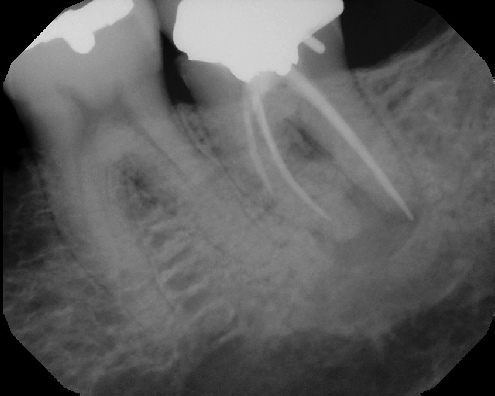

COMPLICATED ANATOMY LARGE LESIONS CALCIFIED CANALS PERFORATION / RESORPTION SEPARATED INSTRUMENTS SURGICAL CASES RETREATMENT / pOST REMOVAL OPEN APICES ACCESS THRU CROWNS Root Canal Case Portfolio